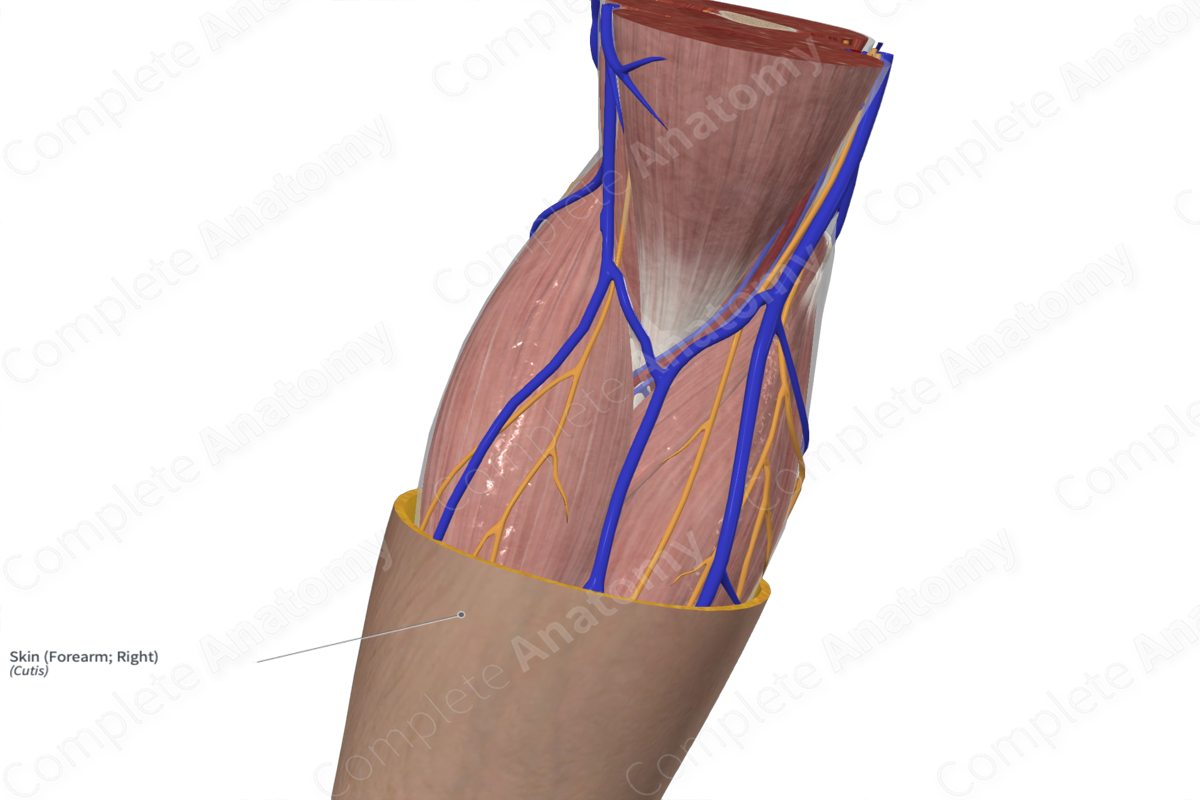

Right forearm online, Skin Forearm Right Complete Anatomy online

Skin Forearm Right Complete Anatomy

1 Complete view of the forearm. Right forearm. Anterior view